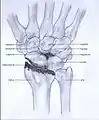

Post-traumatic osteoarthritis can be classified into four stages.[1][6] These stages are similar between SLAC and SNAC wrists. Each stage has a different treatment.

- Stage IV: the osteoarthritis is located in the entire radiocarpal joint and in the intercarpal joints. It also may involve the distal radio-ulnar joint (DRUJ).

Stage IV